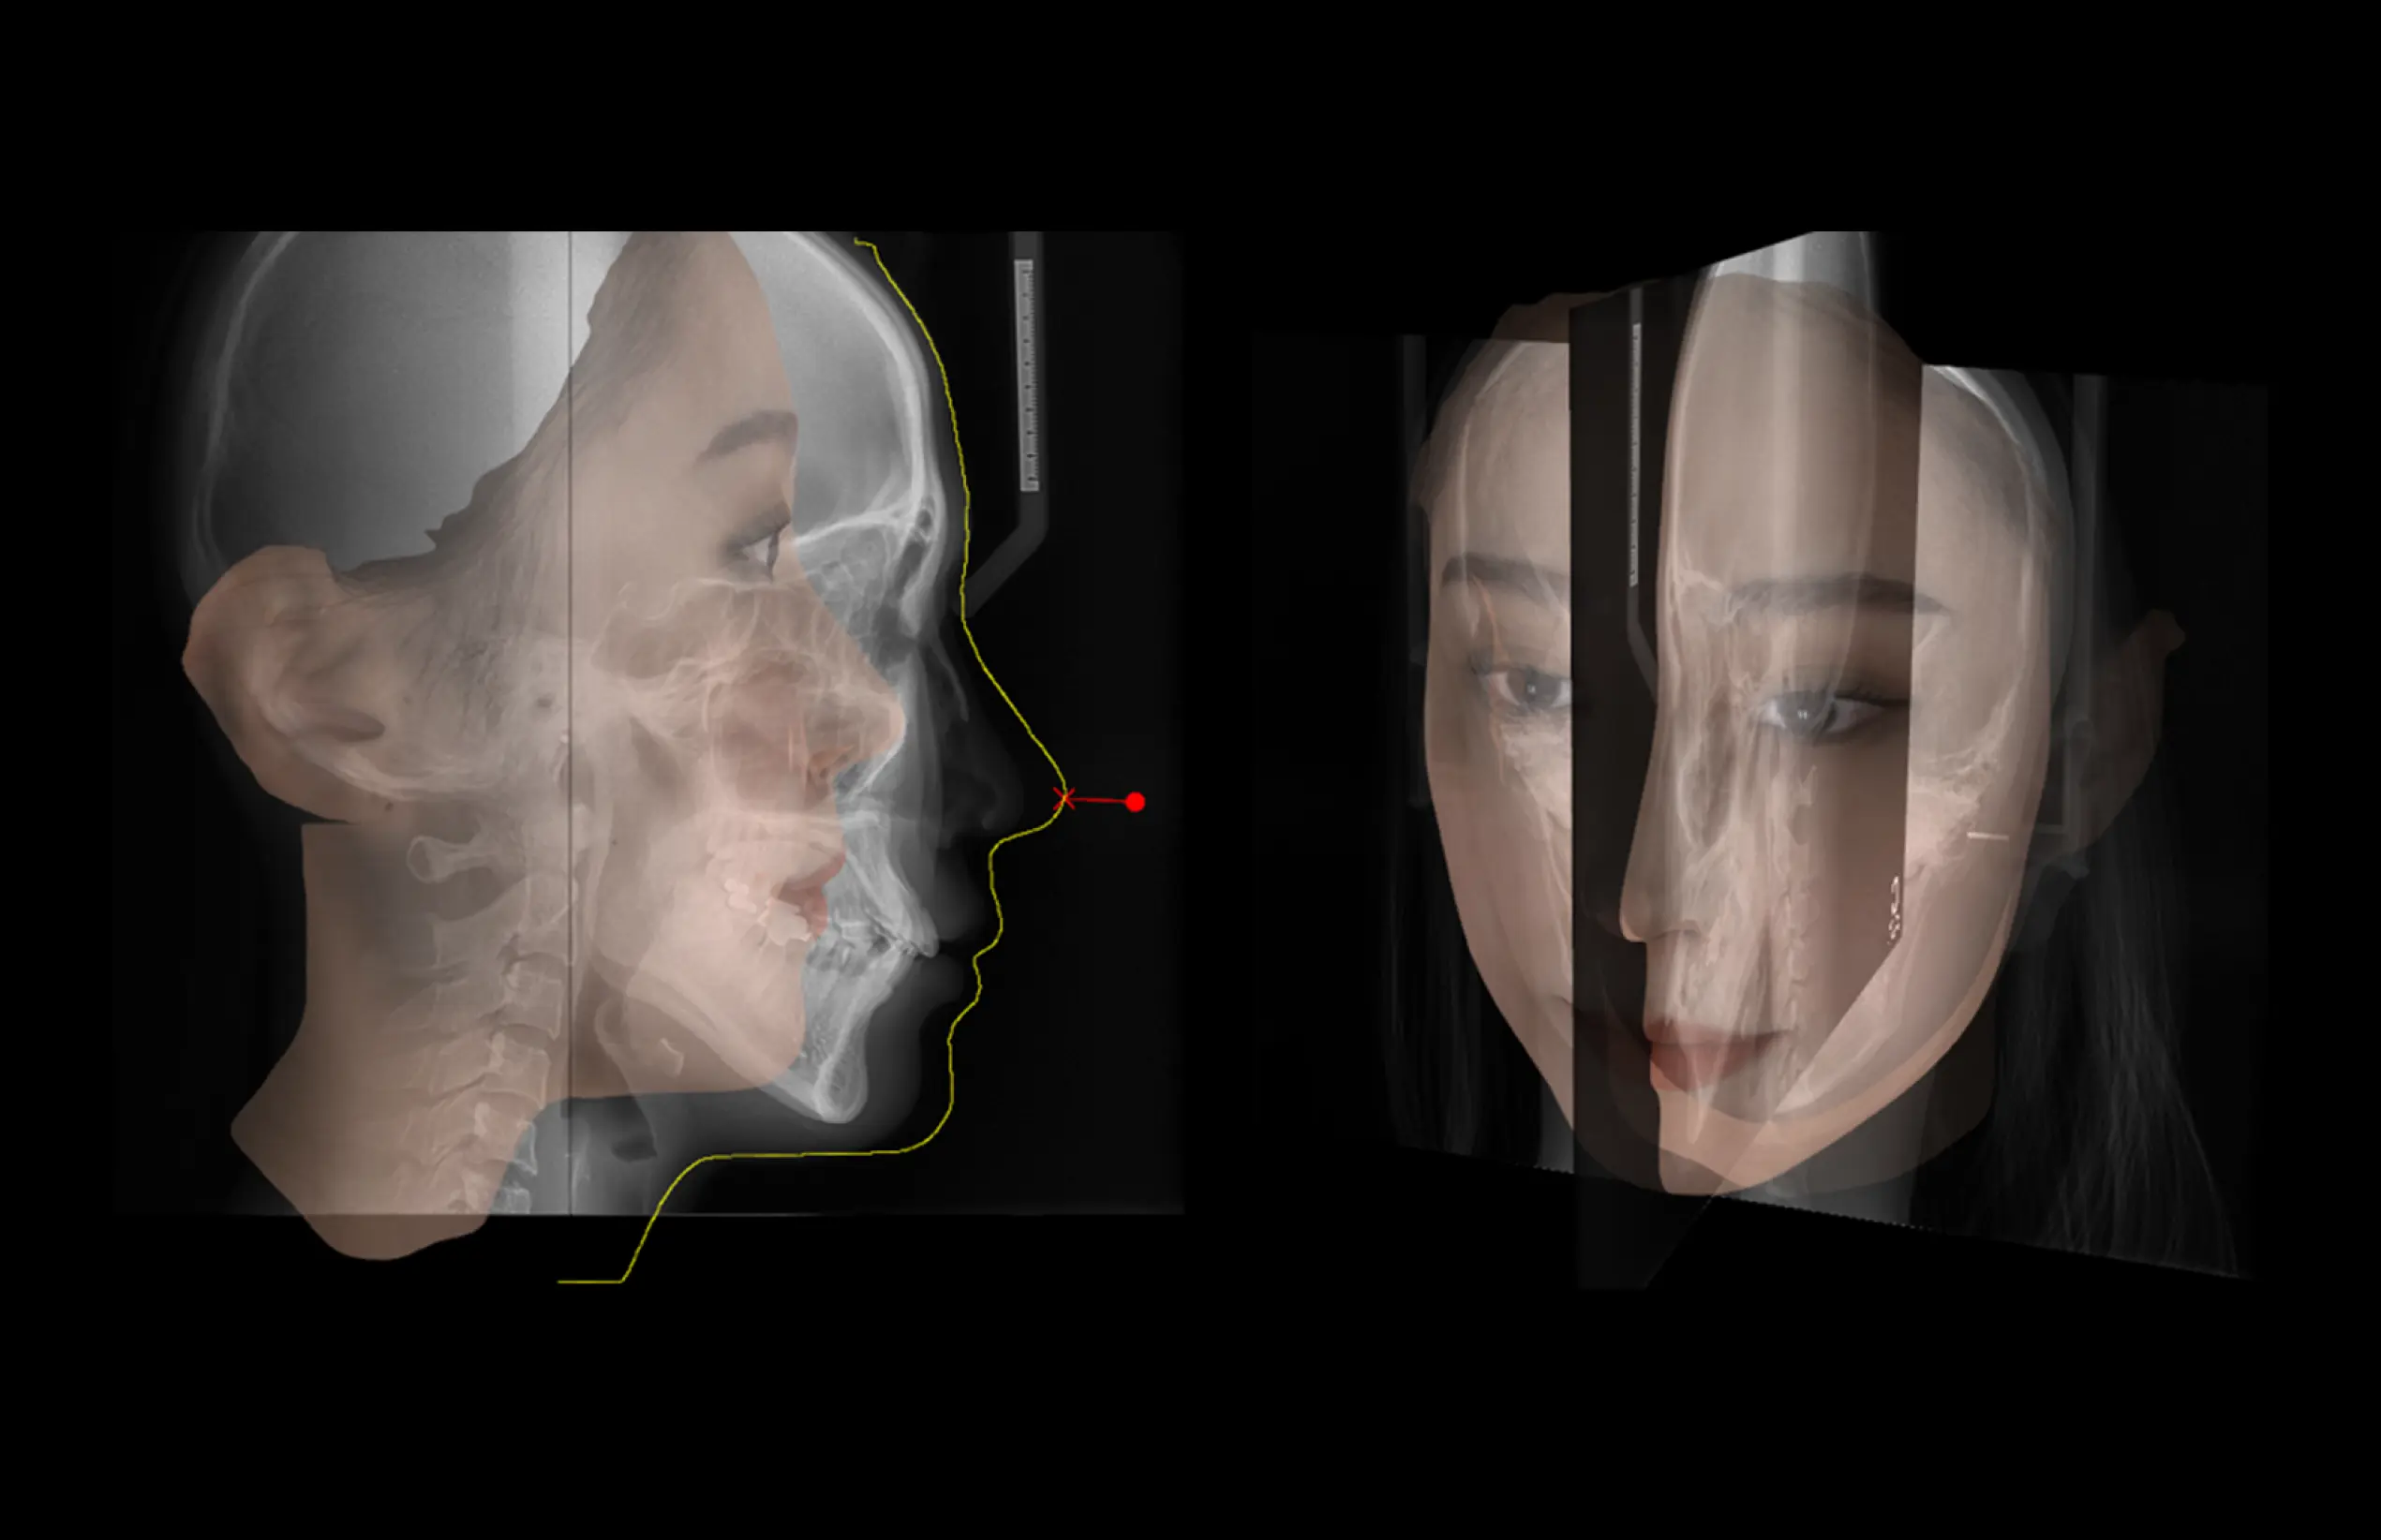

MDSDental Solution

더보기 오토 트레이싱

·환자의 X-ray (측면 & 정면)에서의 디지털

트레이싱

·클릭 한번으로 빠르고 정확한 AI기반의 자동

트레이싱